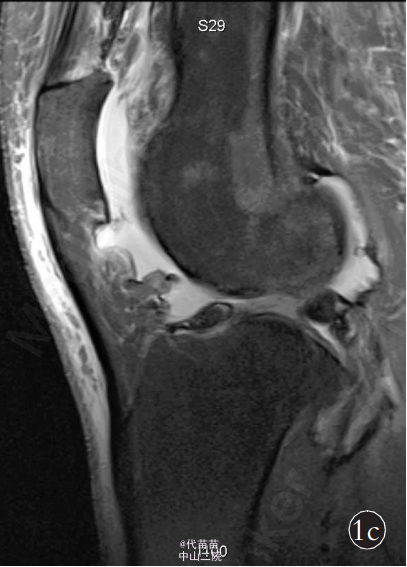

患者,女,70岁 。主因右膝关节间断性疼痛4年,加重2个月入院。患者自诉4年前无明显诱因出现膝关节间断性疼痛,活动时疼痛加重,休息后症状缓解,同时伴有右膝关节肿胀,膝关节活动时弹响症状明显,无夜间痛,未系统治疗。近2个月来患者疼痛症状逐渐加重,不能完全蹲下,并出现右小腿轻度肿胀。患者既往体健。查体:右膝关节肿胀,无发红及包块。右膝关节间隙按压痛阳性,浮髌试验阳性,髌骨摩擦试验阳性,右膝关节活动度:0°~130°,右下肢肌力Ⅳ级,其他检查未见异常。 影像学检查:X 线片示右侧膝关节不对称性变窄,关节面硬化,边缘可见唇样骨质增生,股骨下端凹槽样改变,边界较清楚,无骨膜反应,髌骨呈槽沟样改变(图 1a)。 右膝关节 CT 示右侧髌骨较薄,髌骨关节面锯齿样改变(图 1b)。MRI检查示膝关节腔内液体增多髌上囊内可见低信号影(图 1c)。为排除肿瘤及感染的可能性,进一步行实验室检查:血常规、ESR、CRP 及碱性磷酸酶以及 ECG 检查均未见异常。完善相关检查后, 择期行全膝关节表面置换术及滑膜清理术。为防止术后股骨缺损处出现病理性骨折,考虑选用制定型膝关节假体(股骨假体柄加长)。术中见:膝关节髌上囊内有大量陈旧性积血(图 1d),滑膜增生肥厚,股骨远端髁部上段可见轮廓清楚的凹陷性骨侵蚀面,股骨及胫骨骨赘形成,股骨髁及胫骨平台关节面软骨破坏,股骨外侧髁破坏严重,部分软骨下骨外露, 髌骨外侧变薄, 髌骨关节面有沟槽样凸凹不平(图1d),软骨面破坏,外侧较重,软骨下骨外露。 术中将病变关节囊及滑膜送检病理,快速病理回报:色素绒毛结节性滑膜炎可能性大。 术中彻底切除髌上囊、滑膜、髌下脂肪垫及半月板,切除胫骨表面、前十字韧带及后十字韧带,处理股骨髁,矫正 FTA 角为外翻 5°,安装 Depuy 公司 2 号股骨假体加长柄及2 号胫骨假体,胫骨假体上安装 8 mm 垫片,复位关节。检查内外侧软组织平衡良好,功能活动良好,此时行髌骨成形术,修理髌骨后见髌骨活动轨迹差, 缝合前向关节腔内软组织注入镇痛药物。 术后右侧膝关节侧位片示:假体固定位置良好,股骨加长柄通过股骨皮质缺损区(图 1e)。 术后病理诊断:色素绒毛结节性滑膜炎(图 1f)。 术后 24 h 拔除负压引流,伸直位